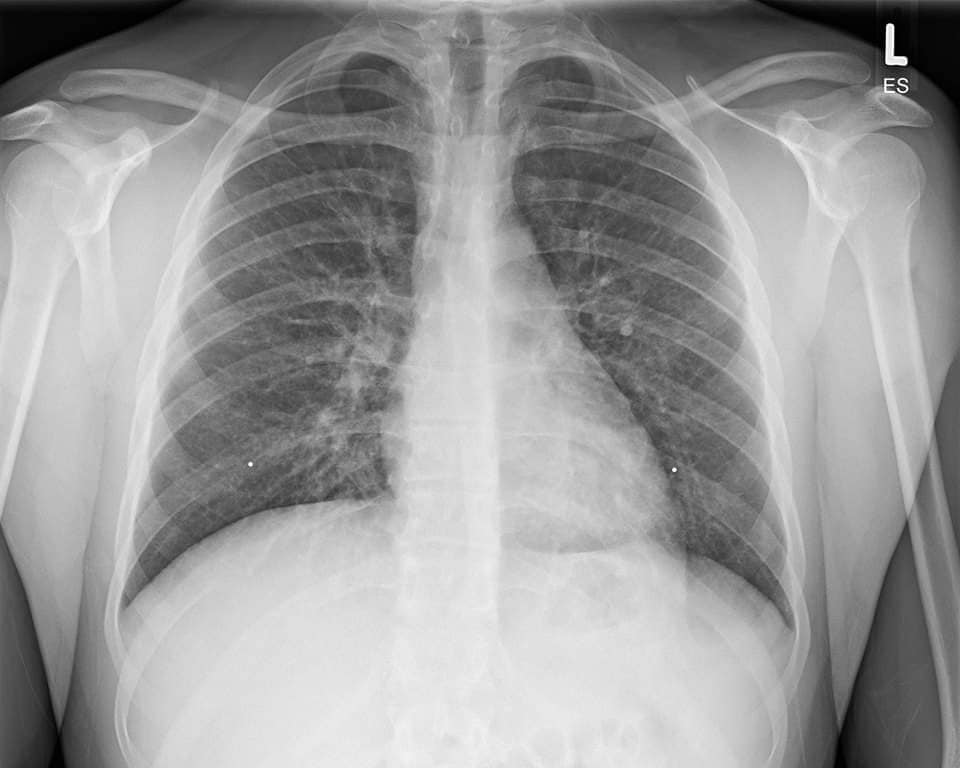

Așa arată plămânii unui tânăr de 20 de ani care în fiecare dimineață bea cafeaua alături de un dispozitiv de vapat. Acesta a ajuns la spital cu dureri și cu senzație de sufocare. Medicii se confruntă cu o boală care face ravagii în rândul tinerilor. Substanțele din țigările electronice și din lichidele pentru vaping cauzează leziuni pulmonare foarte grave.

Așa arată plămânii unui tânăr de 20 de ani care în fiecare dimineață la cafea, își aprindea și o țigară electronică

Evali este boala asociată E-cigarette și produselor de vapat, iar medicii trag un semnal de alarmă pentru că afecțiunea pulmonară pe care o provoacă poate fi fatală. Aceasta este postarea pe care un medic din București a făcut-o pe rețelele de socializare, îngrozit de ce a putut să vadă pe radiografia pulmonară a tânărului pacient.

„Bună dimineața la cafeluță și la țigară electronică. Aceștia sunt plămânii unui tip în vârstă de 20 de ani, care fumează țigară electronică. A ajuns la spital cu dureri și cu senzația de sufocare. Boala este una relativ nouă și se numește Evali, adică E-cigarette or Vaping Product, Use Associated Lung Injury. Adică leziuni pulmonare provocate de substanțele din țigările electronice și din lichidele pentru vaping. Se și moare din cauza lor. Deci când vă mai spune cineva de la IQOS sau Glo că țigările electronice sunt sănătoase, să-i arătați pozele astea și să-i spuneți să plimbe ursul.

La fel și când vedeți firme sau site-uri unde scrie fumează sănătos. Nu există fumat sănătos. Și mai dramatic este că țigările electronice sunt foarte populare printre minori. Industria tutunului știe asta și se bucură. E tot ce-și dorește: cât mai mulți dependenți de nicotină, care să o îmbogățească și mai mult. O altă problemă este că cele mai vehemente reacții la postarea asta sunt de la fumătorii care încearcă să se convingă că e bine să fumezi sau de la vânzătorii de țigări electronice. Realitatea e fix asta din imagini”, a transmis Robin Simion pe rețelele de socializare.